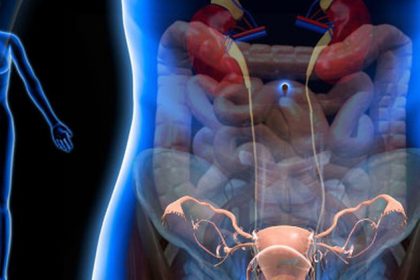

These Painkilling Cannabis Tampons May Be The End of Period Cramps : The Hearty Soul

CBD is gaining recognition as an effective medicinal product for treating various…